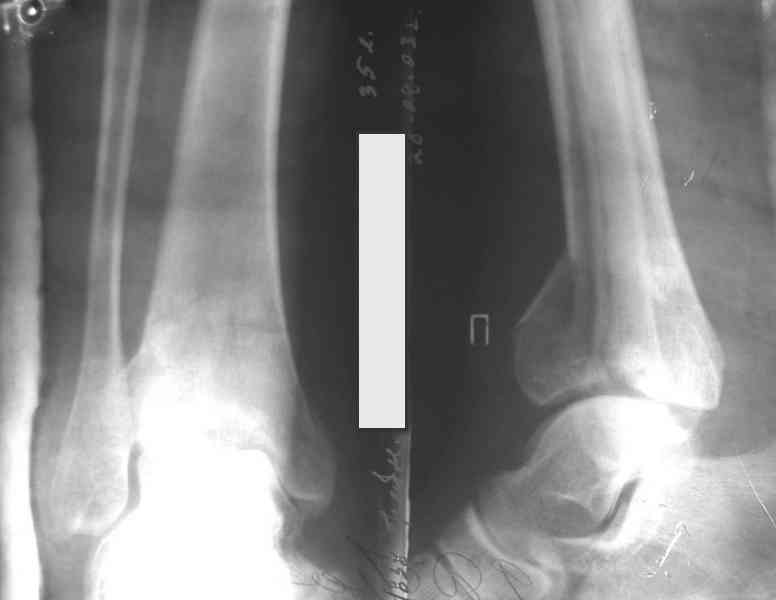

Послала ещё два снимка, если не пройдут, пошлю ещё. Дрягин. Если есть вопросы, готов ответить.